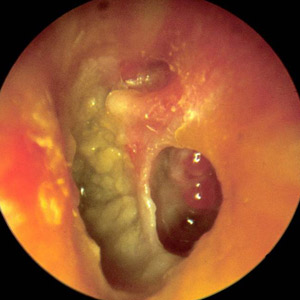

feuchtes Ohr

Entzündungen des Mittelohres sind charakterisiert durch permanente oder immer wieder kehrende Absonderungen aus dem Ohr (Ohrenlaufen) oder Ansammlung von Flüssigkeit hinter einem intakten Trommelfell. Durch die entzündliche Schwellung der Schleimhaut im Mittelohr, durch das Sekret und gelegentlich auch durch eine Zerstörung von Teilen der Gehörknöchelchen kann eine Schwerhörigkeit entstehen. Schmerzen werden eher selten von Betroffenen berichtet, da das meist vorhandene Loch im Trommelfell verhindert, dass sich die Flüssigkeit und der Eiter im Mittelohr stauen.